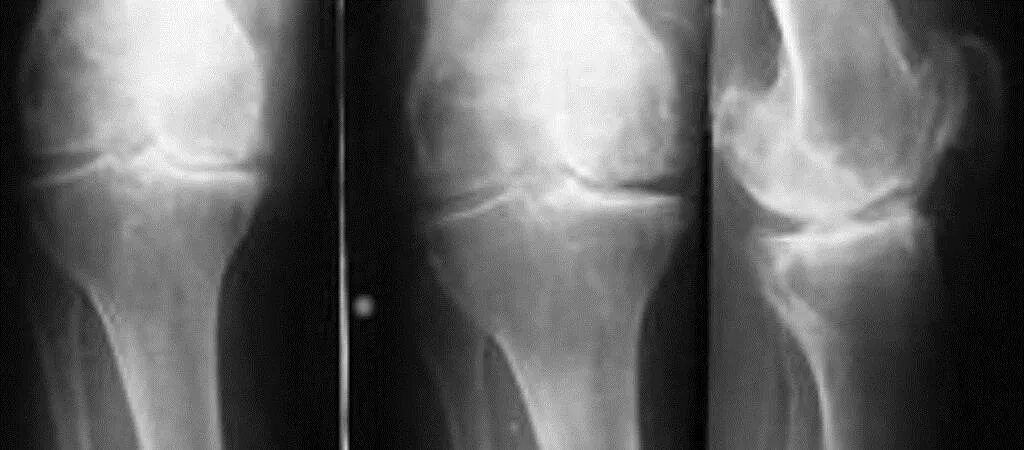

Артрит суставов стадии